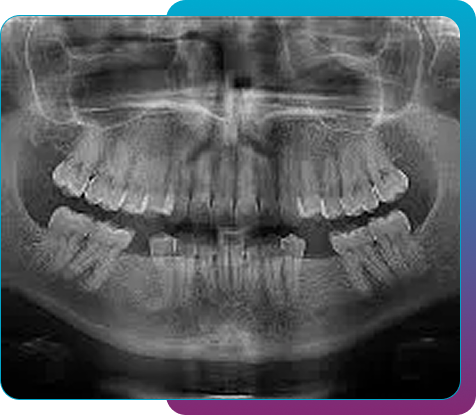

Panoramic Xray